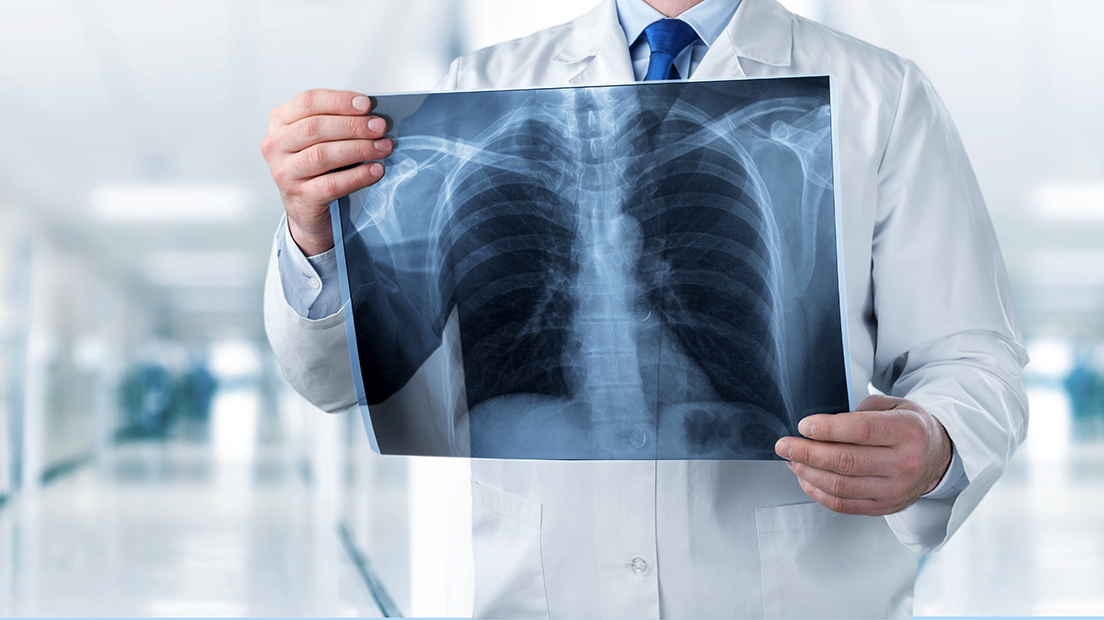

XSAY Teleradiology, established in 2017, aims to empower healthcare organizations across Saudi Arabia and the region by offering access to highly qualified subspecialized Saudi radiologists. The company’s mission is to bridge the gap in radiology services, particularly in underserved areas, by providing expert diagnostic imaging interpretation through advanced telecommunication technologies. XSAY focuses on delivering high-quality, timely, and accurate radiological reports, making it easier for healthcare providers to obtain expert opinions that will make a difference. XSAY aims to streamline the diagnostic process, ensuring that patients receive the comprehensive care they need. Committed to innovation and excellence, XSAY Teleradiology stands as a trusted partner in the evolving landscape of healthcare.